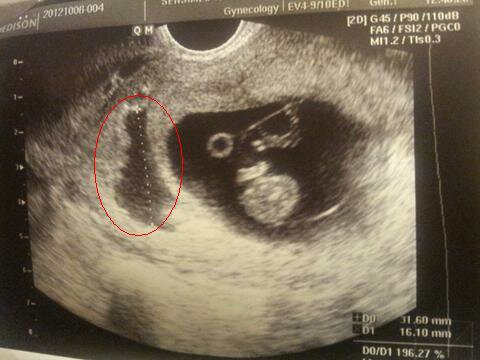

Miałam podobna sytuacja a nawet mam zdjęcie z usg i lekarz mi powiedział to samo że albo "wyplynie" dziecko albo krwiak i ze teraz jest taka konkurencja kto jest silniejszy. W moim przypadku skończyło się dobrze dlatego krwawilam!! Ale powiedział że w takiej sytuacji krwawienie oznacza dobrze ze krwiak opuszcza nas.Na usg jest mały krwiaczek. Około 12 mm.. No ale dzidziuś 7 mm, więc jeśli by pękł to dzidziuś nie da rady. Leżę z wenflonem w ręce i czekam. Dziękuję za ciepłe słowa

@MagMag to zdjęcie mojej córki z krwiakiem ! Tak wyglądało tragicznie a skończyło się wszystko dobrze